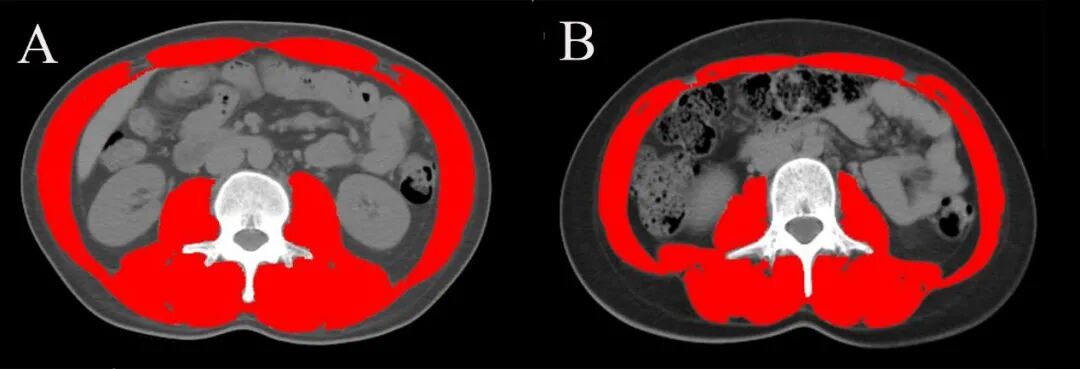

图2 在(A)26岁,BMI 21.6 kg/m2男性和(B)20岁,BMI为20.9 kg/m2女性第三腰椎(L3)腹部CT扫描图片

第三腰椎(L3)水平的CT图像由放射科医生从医学影像管理系统中导出,由肝病科医生使用图像分析软件SliceOmatic进行测量。使用HU阈值-29—+150对图像中的全部肌肉进行识别和量化(包括腰大肌、竖脊肌、腰方肌、腹横肌、内外斜肌和腹直肌)。软件自动计算该层肌肉的总面积,用身高的平方校正后,得到第三腰椎骨骼肌指数(SMI,cm2/m2)。所有图像均由两名肝病科医生进行测量,一名肝病科医生测量图像两次以进行一致性检验。